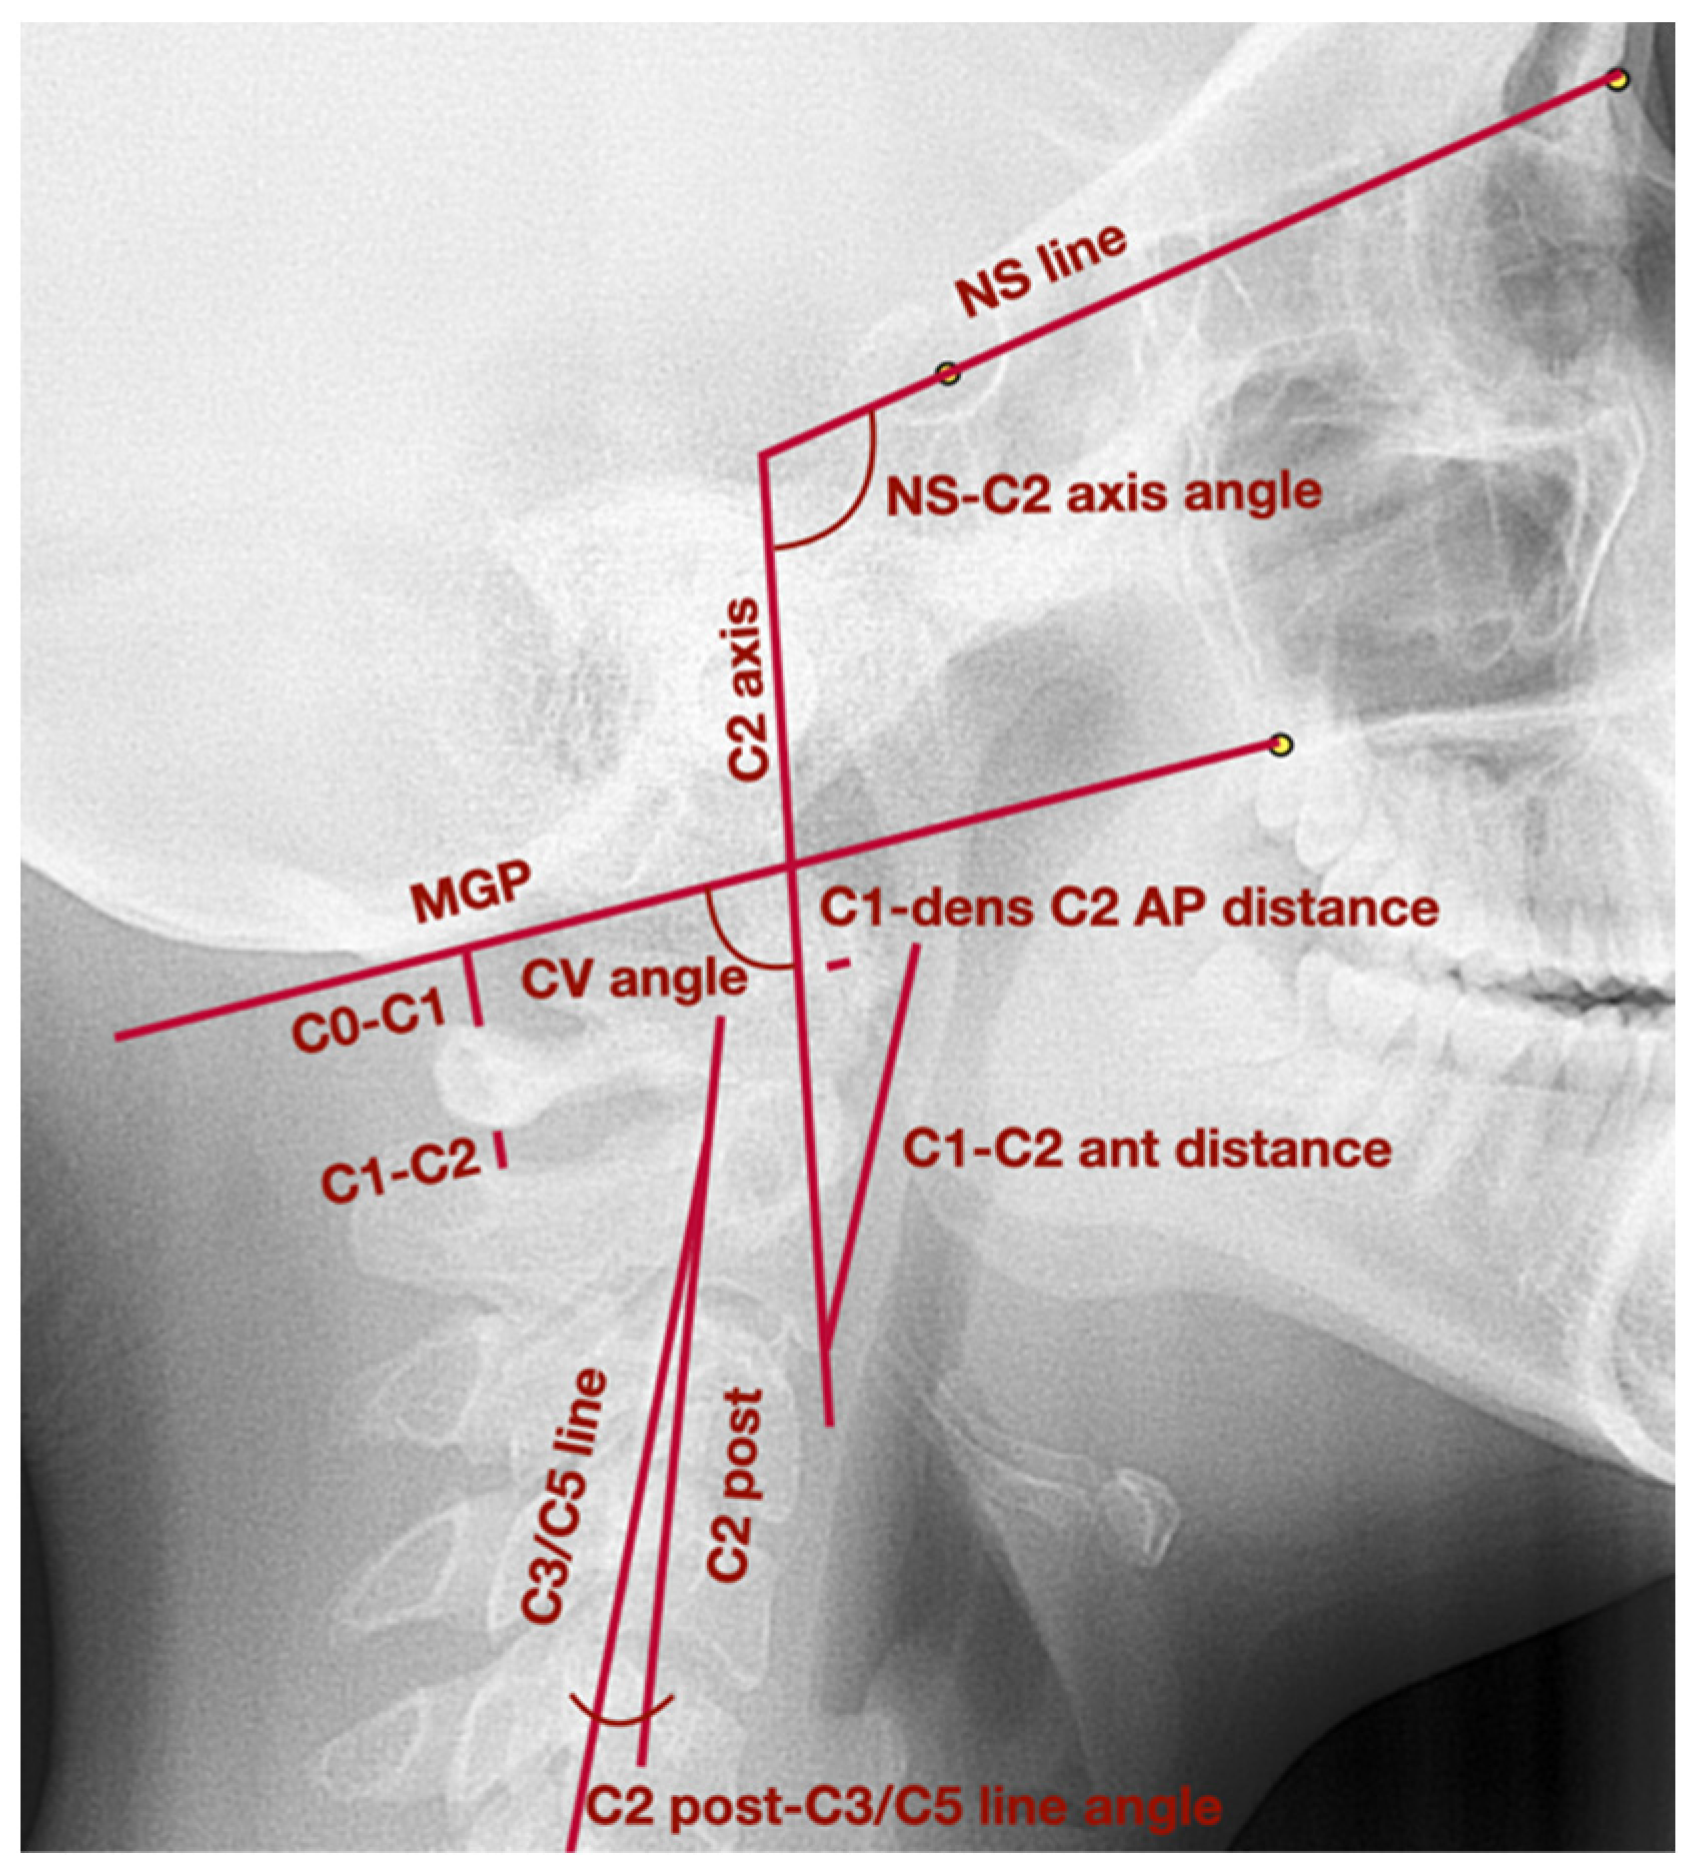

| C2 axis | Long axis of C2 vertebra, which crosses the apex of the odontoid process and the most inferior anterior angle of the body of the second cervical vertebra | |

| C2 post | Line tangent to the posterior wall of the odontoid process of the second cervical vertebra | |

| C3/C5 line | Line which links the most posterior superior angle of the body of the third cervical vertebra with the most posterior inferior angle of the body of the fifth cervical vertebra | |

| MGP | McGregor’s Plane—line which links posterior nasal spine with the basiocciput | |

| NS line | Line which crosses the points: nasion and sella | |

| Head position and cervical vertebrae | CV angle | The posterior angle between the lines: C2 axis and MGP |

| C2 post-C3/C5 line angle | The angle between the lines: posterior wall of C2 odontoid process and C3/C5 line; the value of the angle is positive when the C2 axis is placed anteriorly to C3/C5 line; when the C2 axis is placed posteriorly to C3/C5 line, the value of the angle is negative | |

| C1-dens C2 AP distance | The anteroposterior distance between anterior surface of the odontoid process and posterior border of the atlas anterior arch | |

| C1-C2 ant distance | The distance between the most anterior point of the atlas anterior arch and the most inferior anterior angle of the body of the second cervical vertebra | |

| NS-C2 axis angle | The anterior angle between the lines: NS line and C2 axis | |

| Cervical vertebrae functional spaces | C0-C1 distance | The distance between basiocciput and superior part of the posterior arch of the atlas |

| C1-C2 distance | The distance between inferior part of the posterior arch of the atlas and superior part of the spinous process of the second cervical vertebra |